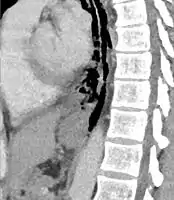

Sagittal remormatted CT image showing discontinutity in the wall of the posterolateral aspect of the distal esophagus